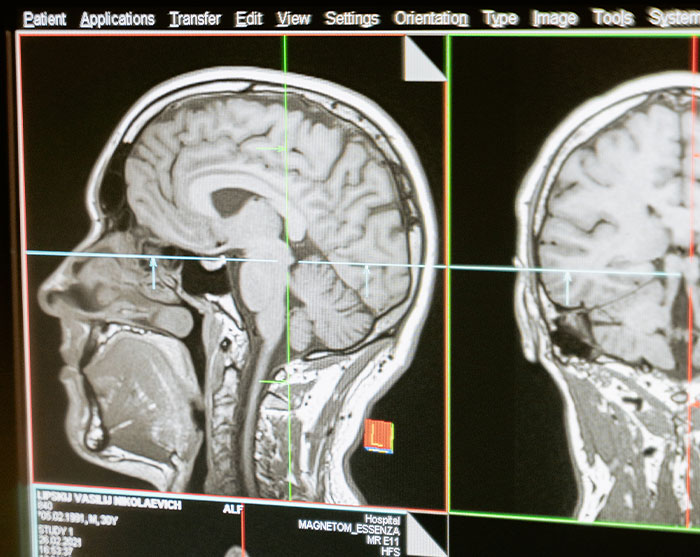

My 33 year old husband was diagnosed with inoperable glioblastoma (most aggressive brain cancer) in January 2019, when he was 31. What caused him to get a check, was persistent headache that didn’t go away with paracetamols and sleep. We discovered the tumours after taking an MRI.Needless to say, our lives were changed forever. Now we are at the end of our journey, and it’s been a harrowing experience for me as his wife and caregiver. It’s a lonely journey. I don’t wish it upon anyone and no one has any idea what glioblastoma is like, unless they have gone through it. The median survival time is 14-18 months. We are on our 18th month now.. and given days/ weeks left. Every day is a gift, and I’m glad I get to be holding his hands every day, even if he’s resting and sleeping most of the time. As long as he is not in pain, and that the morphine patches are working, that is fine by me... I can’t handle him going through anymore pain.

My brother was 11 when he started experiencing symptoms. He started losing a lot of weight, and when he was playing soccer it looked like he was running through mud and couldn’t keep up with everyone else. My parents took him to the pediatrician and they couldn’t figure out what was wrong. One day, he woke up and couldn’t stop throwing up. When he tried to run to the bathroom, he kept running into the door frame and couldn’t walk straight. He said the lights were giving him a headache. We took him to the emergency room and they found that he had a brain tumor, and had emergency brain surgery the next day. We were extremely lucky that they decided to do a CAT scan at the ER, apparently they don’t usually do them on kids.Two brain surgeries and a year and a half of chemo later, and he is in remission now!

Seizures in my sleep. Had been living a very healthy lifestyle while in my first year of law school and then all of a sudden I started getting seizures in my sleep. I immediately went to my primary care and was sent to the hospital for scans. Results came back the same day and was told to go to the neurologist ASAP and that’s when I was told about the tumor growing in my brain.Edit: I’d like to add that I’d had migraines since I was like 17, but my GP told me it was probably because of periods since that was usually the case with women. It wasn’t until I had my first gran mal seizure that he took things seriously. IF YOU HAVE CHRONIC MIGRAINES, PLEASE FOR THE LOVE OF GOD SUGGEST AN MRI. Just to rule out whether it’s a tumor or not.

I had what I thought was a stroke and found out I have a Glioblastoma. I was given 12-15 months and so far I’ve made it to the 15th month!